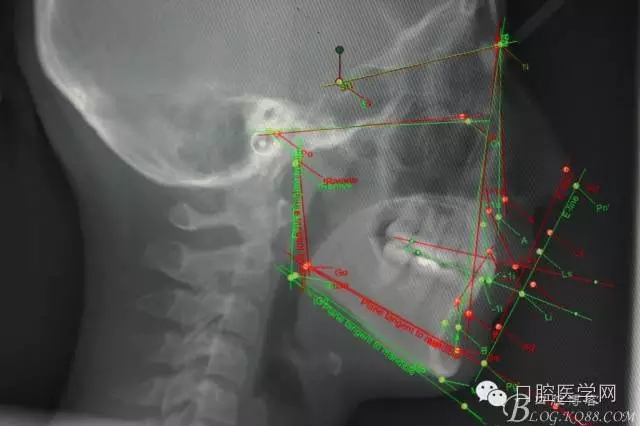

正畸前后頭顱側(cè)位SN平面和S點(diǎn)重疊圖: